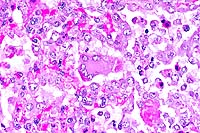

- Case 24-3. Haired skin. The dermis and subcutis beneath

a thickened epidermis is expanded by edema and infiltrating inflammatory

cells which surround and separate normal dermal elements. High

power of the epidermis illustrates multiple brightly eosinophilic

intracytoplasmic inclusions within keratinocytes, multifocal

neutrophilci infiltrates, and parakeratotic hyperkeratosis.